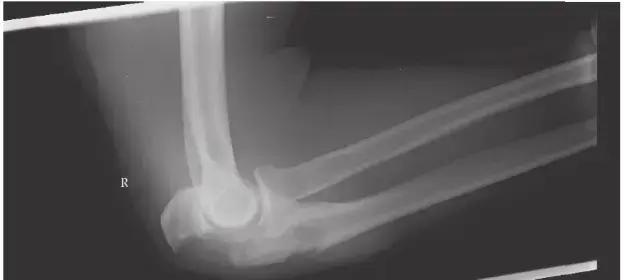

🔗 اقرأ الدليل الشامل: تعرف على كسور الكوع أوليكرانون: الأسباب، الأعراض، وطرق العلاج الفعالة